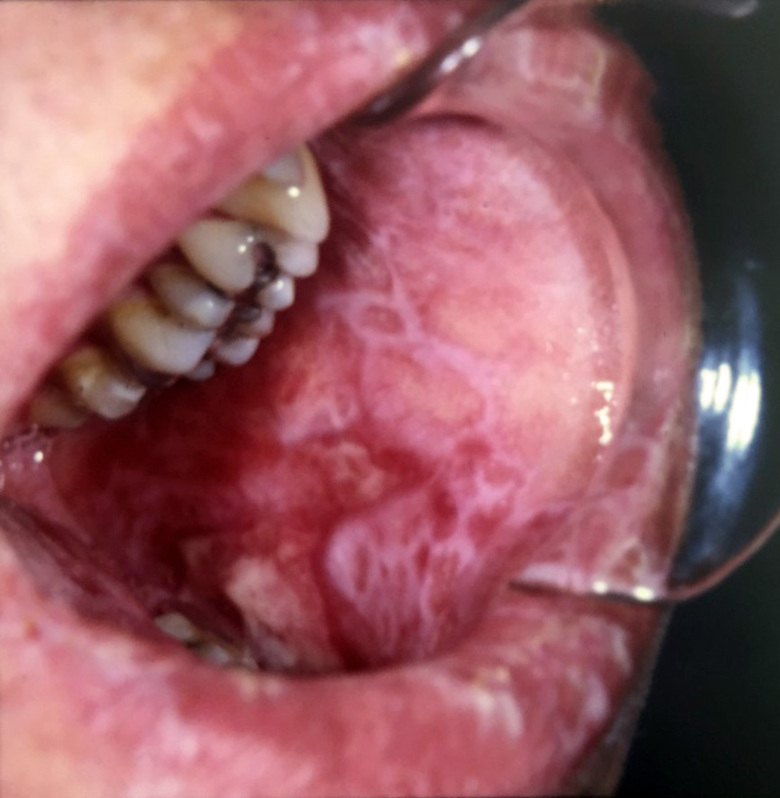

Principally, we focus on the complications that result following hematopoietic stem cell transplantation in the form of Graft versus Host Disease (GVHD), which is a major cause for morbidity and mortality (~70%) in these patients. Oral manifestations are one of the most common and debilitating complications, with a diverse spectrum of clinical features, including mucosal lesions, salivary gland dysfunction and restricted mouth opening. Patients may experience mucosal sensitivity, oral pain, increased caries risk, malnutrition and problems speaking and long-term, complications include secondary malignancies and mortality. Current treatments alleviate symptoms but due to a general lack of understanding of oral chronic (c)GVHD, from clinical signs to histopathological diagnoses, the development of treatment regimens is slow. The research group is focusing their efforts on trying to improve clinical diagnoses by incorporating histopathological guidelines for oral cGVHD pathogenesis together with elucidating the underlying disease mechanisms.

In addition, studies investigating other pre-malignant and malignant oral diseases are ongoing, including mucositis, oral lichen planus, leucoplakia.

We aim to define the histopathological alterations of cGVHD in oral mucosal tissues and salivary glands. In a large cohort, we have devised a histological severity grading scheme for oral mucosal cGVHD lesion diagnostics, and we are also grading the pathological presentation of salivary gland cGVHD manifestations. In both, oral mucosa and salivary gland tissues we are assessing their immunological infiltrate and using digital quantitative immunohistochemistry to relate the histopathological presentation to clinical disease severity.

Clinical staging of cGVHD with aligned histopathological presentation

In this project, we aim to correlate clinical signs and symptoms of oral cGVHD with histopathological features and systemic issues, to define clearer oral mucosal and salivary cGVHD diagnostic criteria. We are assessing the current clinical diagnostic tools for oral cGVHD, with respect to other complications, such as infections and any development of secondary cancer. Altered clinico-histopathological screening will lead to improved management and treatment options. In conjunction, we are employing our new histological grading modules for oral mucosa and salivary gland oral cGVHD to validate their diagnostic potential and coupling them to the clinical presentation, with the goal to provide improved diagnostics.